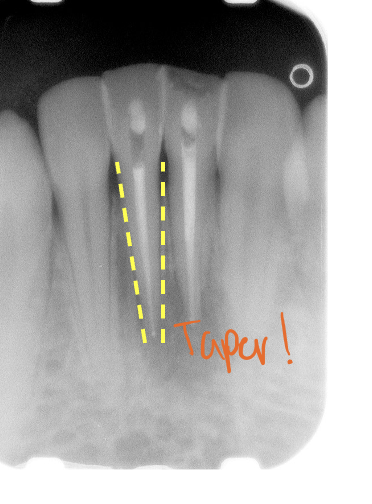

All incisors, root tapers where

TOwards apex